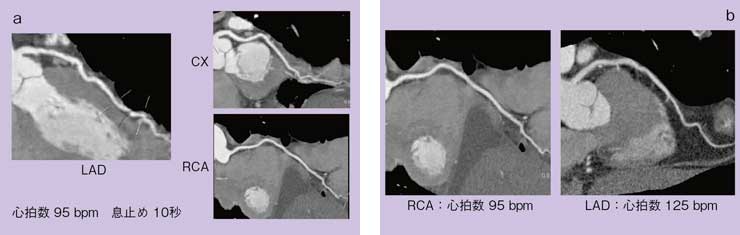

はじめに,当院におけるDSCTで撮影した症例画像を提示する。図1は,左冠動脈画像であるが,末梢の細い血管まで明瞭に描出されている。図2は,頻脈症例の画像である。βブロッカーを用いることなく,心拍数95bpm(a)の患者でも明瞭な画像が得られ,不整脈のある125bpm(b)の患者でも診断可能な画像が得られている。

図2 DSCTによる頻脈症例画像